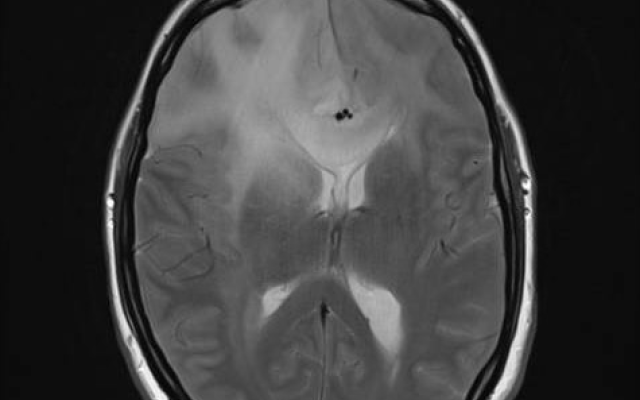

Het komt zelden voor, maar als een vrouw tijdens de bevalling haar bewustzijn verliest, is dat een ernstige complicatie. De differentiaaldiagnose is breed en neurologisch onderzoek is noodzakelijk om organische oorzaken uit te sluiten of aan te tonen. Wij beschrijven hier een 36-jarige patiënte die tijdens de bevalling 5 kwartier buiten bewustzijn leek. Uiteindelijk bleek haar toestand te berusten op een conversiestoornis.

Patiënt A, een gezonde 36-jarige vrouw, gravida 4 para 2, met een amenorroeduur van 41 weken en 3 dagen, was poliklinisch aan het bevallen onder leiding van haar eigen verloskundige toen ze plotseling wegraakte. Met een druk op de noodbel schakelde de verloskundige de gynaecoloog in. Bij binnenkomst troffen we een patiënte aan die ogenschijnlijk buiten bewustzijn was en niet reageerde op aanspreken. De verloskundige vertelde dat patiënte 8 cm ontsluiting had en dat ze kort voor het bewustzijnsverlies hyperventileerde. Ze had geen klachten…